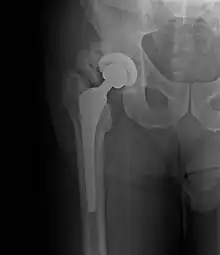

Heterotopic ossification around the hip joint in a patient who has undergone hip arthroplasty